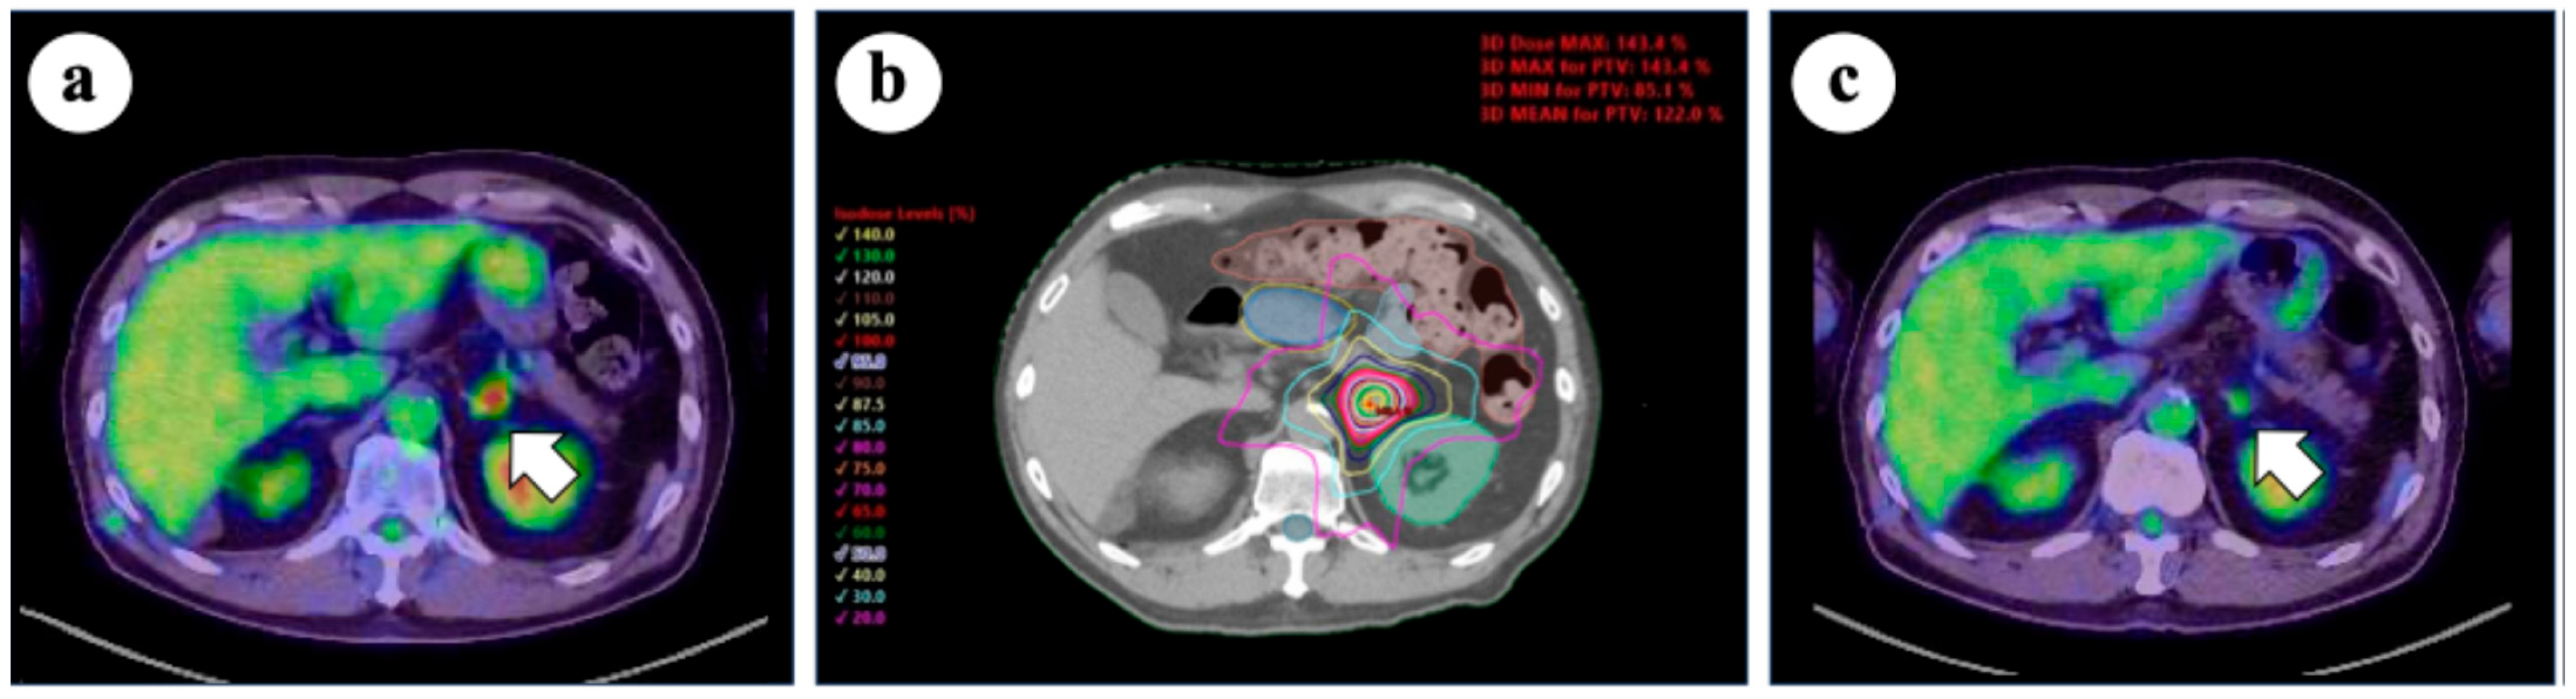

Adrenal SBRT is particularly challenging because of the proximity of the adrenal glands to critical structures such as the upper gastrointestinal tract, liver, and kidneys. Therefore, careful treatment planning is essential to balance efficacy with safety. In Japan, a survey conducted by the Subcommittee of the High-Precision External Beam Radio-therapy Group of the Japanese Society for Radiation Oncology reported that a dose of 35–40 Gy in five fractions prescribed to 95% of the PTV has become a common practice [65]. When the target lesion is close to critical structures, a dose of 35 Gy in five fractions is often used to ensure safety. Based on this approach, prescribing the 60–80% isodose line to increase the tumor dose represents a practical method in clinical settings. Figure 2 shows the representative dose distribution of SBRT for adrenal oligometastases of lung cancer. Safe and effective delivery of adrenal SBRT requires attention to detail, including the use of four-dimensional CT, image-guided radiotherapy, breath-hold techniques, and tracking systems. In a meta-analysis by Liao et al. (involving 915 patients with lung cancer out of 1483 total cases [60.6%], median BED [α/β = 10 Gy]: 71.4 Gy), the use of tracking techniques was associated with improved OS. These findings highlight the importance of technological advancements in precision SBRT for adrenal metastases [66]. Although it remains uncertain whether these advanced SBRT techniques directly improve patient outcomes, further prospective studies are needed to clarify their impact. Nevertheless, the careful implementation of precision-guided techniques is essential for the safe and effective delivery of adrenal SBRT.

Figure 2.

(a) 18-fluoro-deoxyglucose positron emission tomography/computed tomography (FDG-PET/CT) before stereotactic body radiotherapy (SBRT), showing increased FDG uptake in the left adrenal gland (arrow); (b) SBRT plan for the left adrenal metastasis. SBRT was prescribed with a dose of 40 Gy in five fractions to 95% of the planning target volume (PTV) and 70% isodose lines; (c) FDG-PET/CT scan 1 year after SBRT, demonstrating response in the treated lesion (arrow). No severe adverse events were observed.